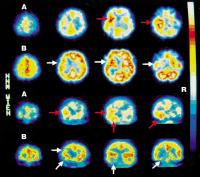

Temorallappenenzephalitis - Läsionen

Abbildung 11: Dynamische Analyse der Läsionsentwicklung bei Temporallappenenzephalitis durch HSV. HMPAO-SPECT